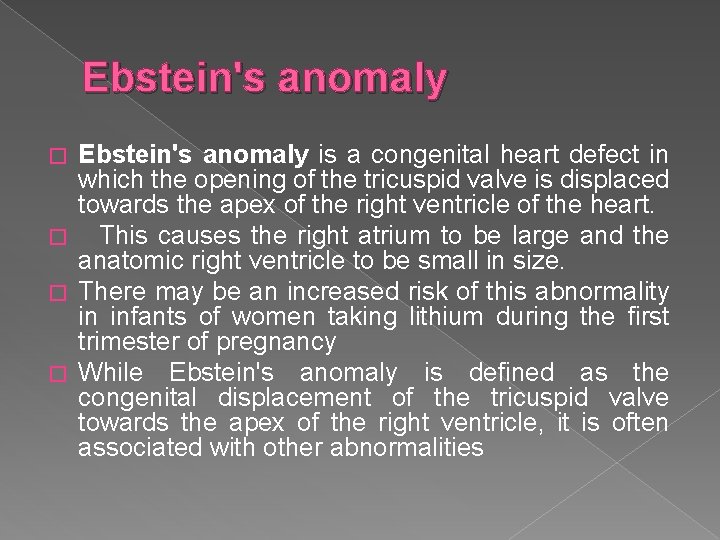

Ebstein's anomaly is a congenital heart defect in which the opening of the tricuspid valve is displaced towards the apex of the right ventricle of the heart. � This causes the right atrium to be large and the anatomic right ventricle to be small in size. � There may be an increased risk of this abnormality in infants of women taking lithium during the first trimester of pregnancy � While Ebstein's anomaly is defined as the congenital displacement of the tricuspid valve towards the apex of the right ventricle, it is often associated with other abnormalities �